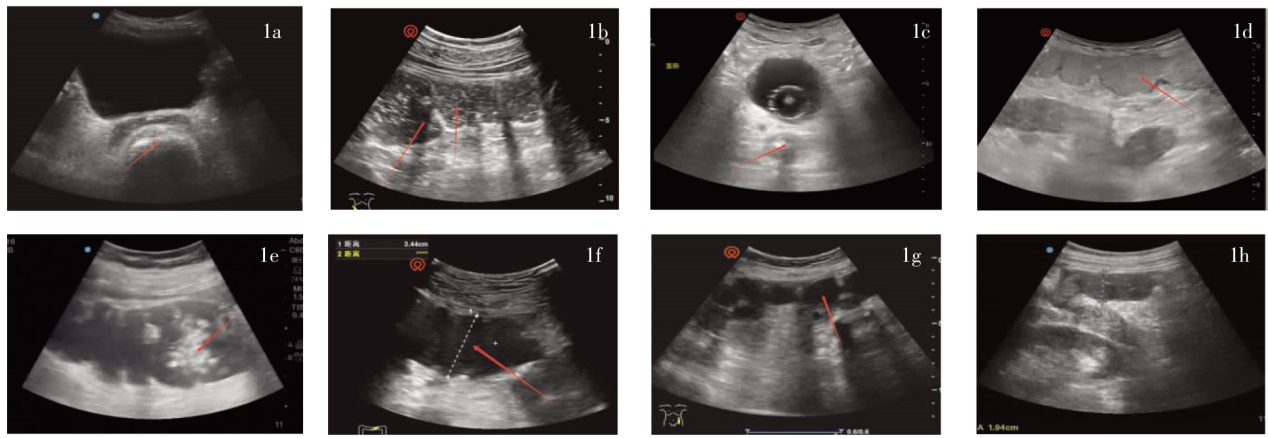

Manabe N, Kamada T, Kusunoki H, et al. Usefulness of ultrasonographic evaluation of stool and/or gas distribution for the treatment strategy of chronic constipation[J]. JGH Open, 2019, 3(4):310-315.

Klijn AJ, Asselman M, Vijverberg MAW, et al. The diameter of the rectum on ultrasonography as a diagnostic tool for constipation in children with dysfunctional voiding[J]. J Urol, 2004, 172(5 Pt 1):1986-1988.

Doniger SJ, Dessie A, Latronica C. Measuring the transrectal diameter on point-of-care ultrasound to diagnose constipation in children[J]. Pediatr Emerg Care, 2018, 34(3):154-159.

Matsumoto M, Yabunaka K, Yoshida M, et al. Improvement of constipation symptoms in an older adult patient by defecation care based on using a handheld ultrasound device in home care settings:a case report[J]. J Wound Ostomy Continence Nurs, 2020, 47(1):75-78.

Joensson IM, Siggaard C, Rittig S, et al. Transabdominal ultrasound of rectum as a diagnostic tool in childhood constipation[J]. J Urol, 2008, 179(5):1997-2002.